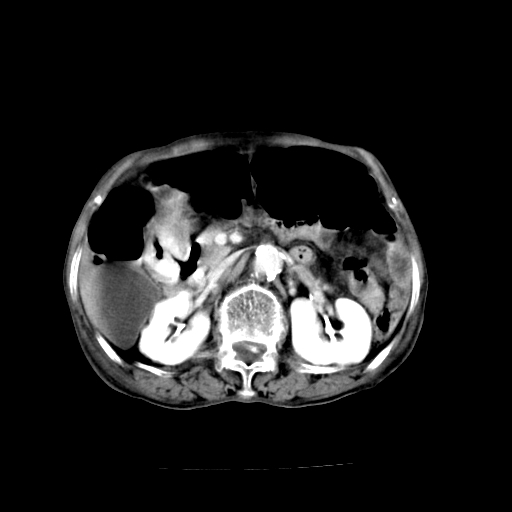

1、胃窦癌; 2、局灶性脂肪肝。

1、胃窦癌?建议行胃镜!; 2、局灶性脂肪肝。

1)胃窦壁厚,考虑胃窦癌?建议行胃镜检查。 2)局灶性脂肪肝。